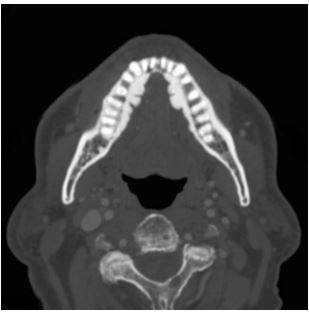

КТ придаточных пазух носа. В полости левой в/челюстной пазухи плотное инородное тело (пломбировочный материал, вышедший из корня зуба).

- Лучевые исследования. При рентгенографии и КТ околоносовых пазух выявляются нарушение пневматизации, затемнение синуса, утолщение слизистой, уровень жидкости и наличие инородного тела. Для лучшей его визуализации данные исследования проводят с контрастированием. При этом инородное тело выглядит как дефект заполнения пазухи. На эхосинусоскопии (УЗИ придаточных пазух) можно обнаружить рентгенонегативные инородные тела.